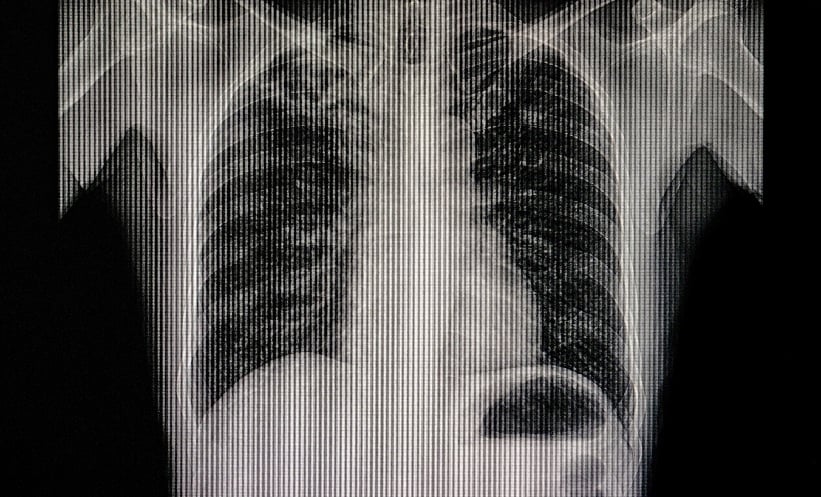

AI-Assisted Chest X-Rays in TB Detection Across LMICs

AI CHEST X-rays could significantly expand tuberculosis detection in low- and middle-income countries (LMICs), where limited imaging access and workforce shortages continue to hinder timely diagnosis. Tuberculosis, a treatable infectious…